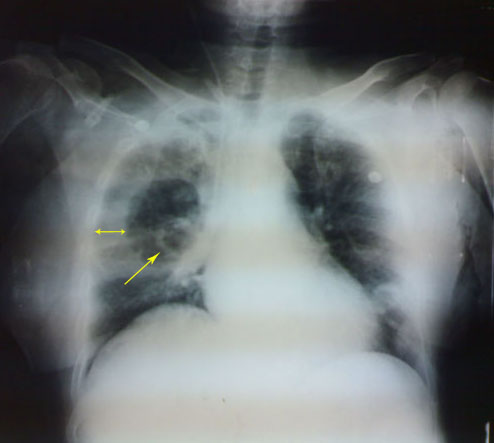

Her plain chest X-ray revealed :

-right lung cavity lesion (see the photo)